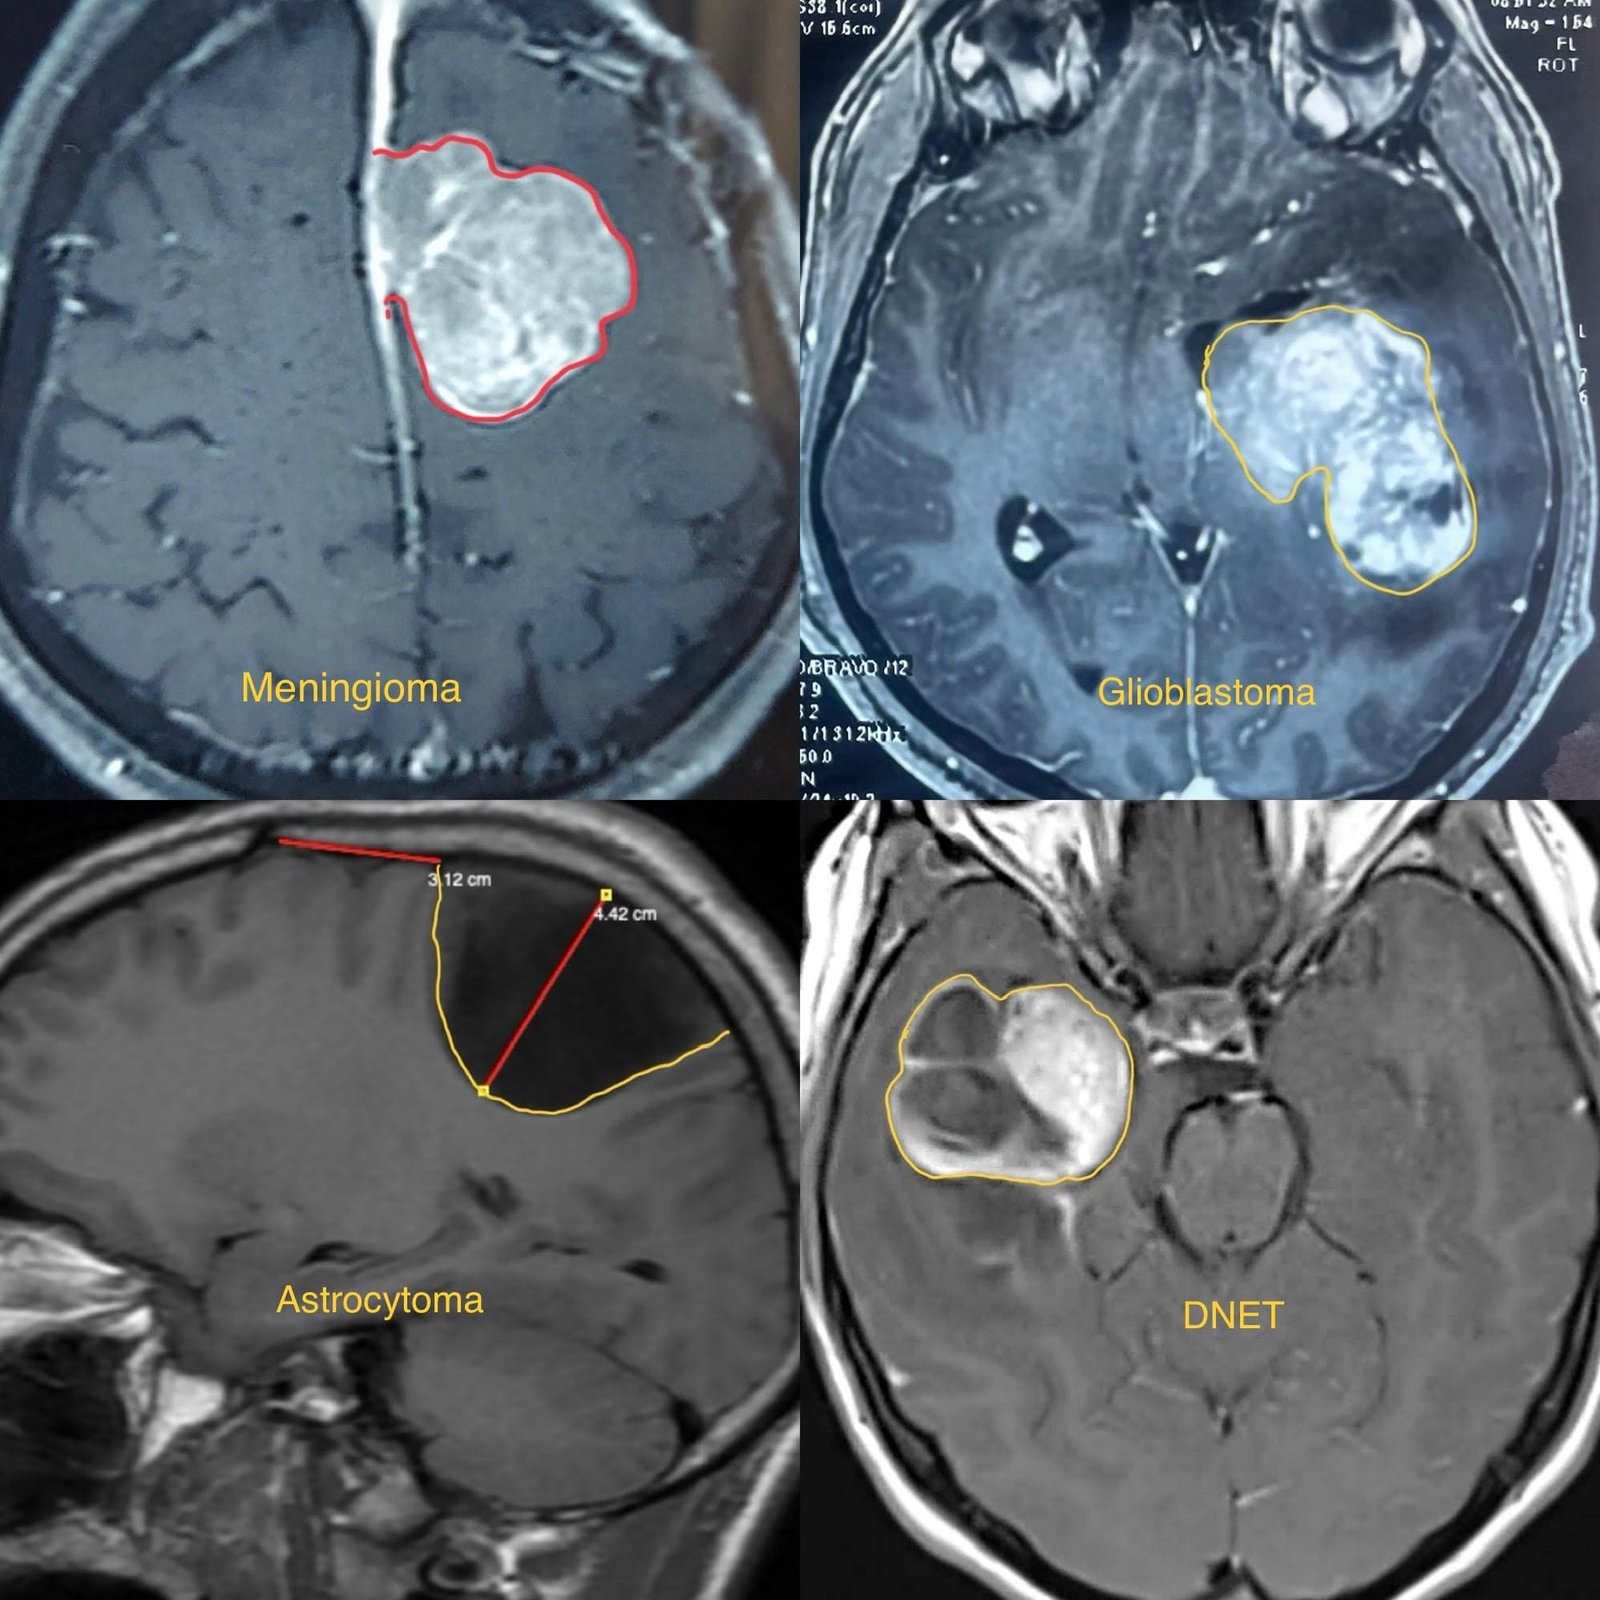

Brain tumors are abnormal growths of cells within the brain. These tumors can be benign (non-cancerous) or malignant (cancerous), and they can originate from brain tissue itself (primary brain tumors) or spread to the brain from other parts of the body (metastatic brain tumors).

• Diagnosis typically involves a thorough neurological examination, medical history, imaging studies such as MRI or CT scans, and sometimes biopsy to determine the type and grade of the tumor.